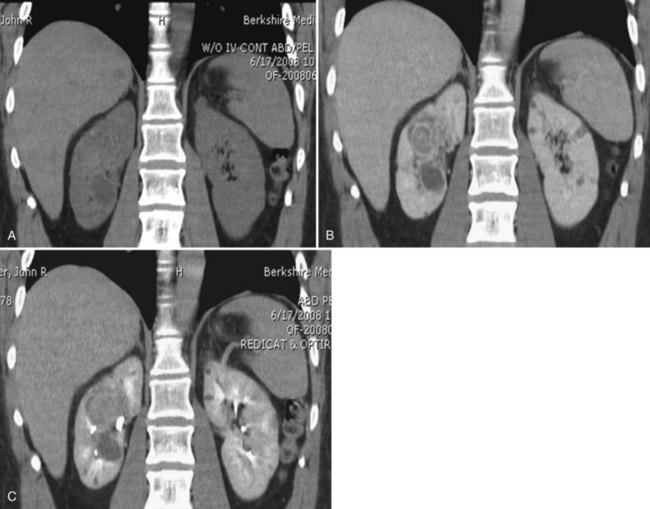

Proposed benefits of preoperative RAE include shrinkage of an arterialized tumor thrombus to ease surgical removal, reduced blood loss, facilitation of dissection due to tissue plane edema, ability to ligate the renal vein before the renal artery at time of nephrectomy, and modulation of the immune response (Klimberg et al, 1985; Bakal et al, 1993; Kalman and Varenhorst, 1999; Schwartz et al, 2007; Wotkowicz and Libertino, 2007; Wszolek et al, 2008). Ligation of the renal vein before the renal artery is useful in the setting of hilar tumors, tumors with significant medial extension, or considerable perihilar adenopathy (Schwartz et al, 2007; Wotkowicz and Libertino, 2007; Wszolek et al, 2008). Before ligating the renal vein, one should characterize the completeness of embolization to prevent unnecessary blood loss in cases of incomplete embolization. In the senior author’s experience this assessment can be made by evaluating renal venous return during surgery. In addition, angioembolization can also be useful for renal tumors associated with large arteriovenous malformations that are having a deleterious hemodynamic impact (Figs. 54-16 and 54-17).

Figure 54–16 Noncontrast (A) and contrast-enhanced (B) CT images of a patient with high output cardiac failure secondary to arteriovenous malformation associated with left renal cell carcinoma. Notice the equal contrast intensity of the aorta, left renal artery, and left renal vein.

Figure 54–17 A, Left selective renal angiogram demonstrates immediate filling of the renal vein and inferior vena cava. B, Angiogram after placement of coils demonstrates complete angioinfarction. Contrast medium in the contralateral renal pelvis confirms contralateral renal function.